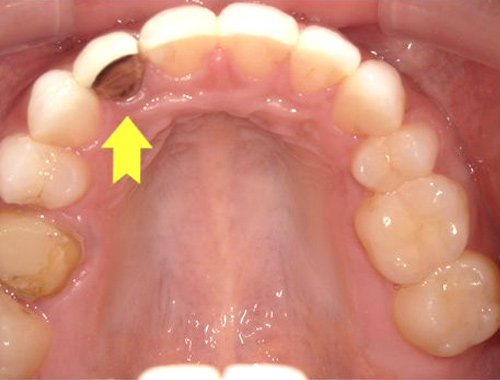

保険診療で使用されていた金属の詰め物(いわゆる銀歯)を、白くて自然な見た目のセラミック(ジルコニア)に変更した症例です。金属の詰め物は強度に優れている一方、笑ったときや口を開けたときに目立ちやすく、長い年月が経つと金属成分が溶け出して歯ぐきが黒ずんで見えることがあります。

それに対し、セラミックの詰め物は見た目がとても自然で、天然歯とほとんど見分けがつかない仕上がりが可能です。金属を一切使用しないため、金属アレルギーの心配がなく、身体にも優しい素材です。

今回使用したジルコニアは、セラミックの中でも特に強度に優れており、歯を薄く削って作製できるという利点があります。一方で、オールセラミックに比べると透明感はやや出にくい素材です。患者さまから「なるべく歯を削らず、強度も確保したい」とのご要望があったため、このジルコニア素材を選択しました。精密に作製されるため適合性にも優れており、しっかりとフィットして虫歯の再発を防ぐ効果も期待できます。

写真では、治療前後の違いをご覧いただけます。黄色い矢印の部分が、実際にセラミックに置き換えた箇所です。治療後は口元の印象が明るくなり、患者さまにも大変ご満足いただけました。

治療期間通院3回(むし歯治療、型取り、セット)、約2週間程度

費用目安税込77,000円×2